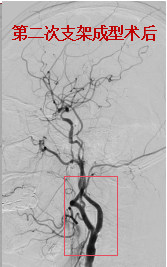

62岁女性,同样因脑梗死、左侧颈动脉狭窄入院。介入团队评估,患者颈动脉狭窄重,且远端负性重构,再灌注出血风险高,建议分期进行支架成型手术,以降低高灌注综合征发生率。两次支架成型术后,颈动脉血管重建良好,术后未发生出血等,患者平稳出院。